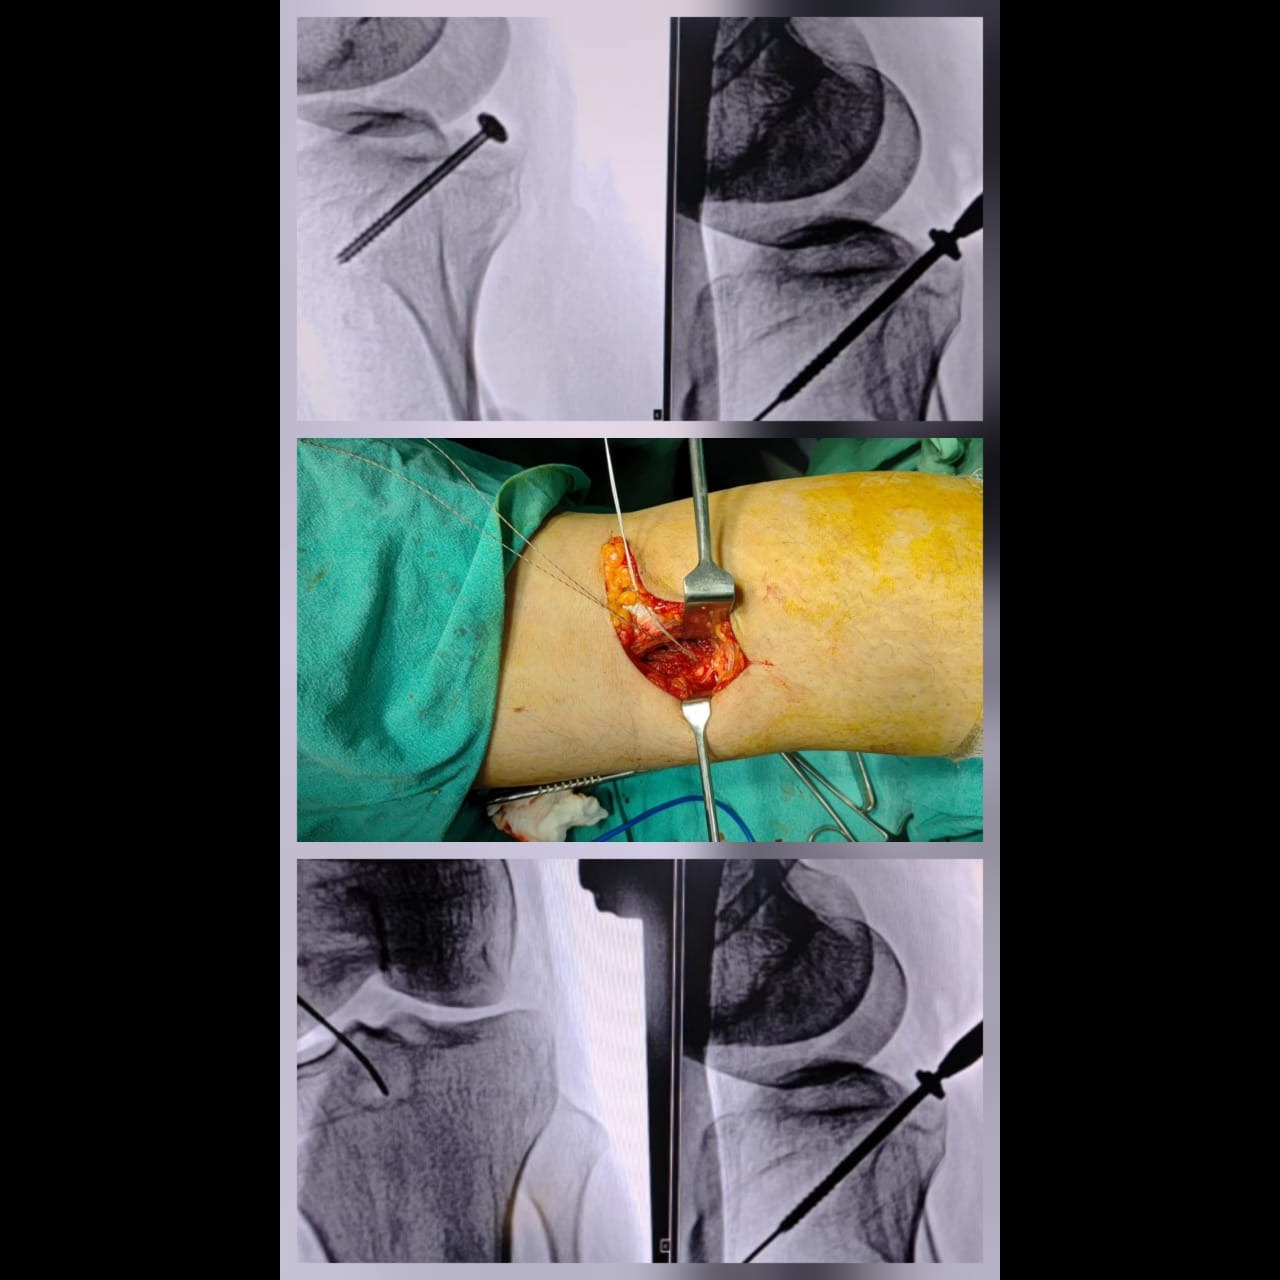

Best Joint Replacement/Orthopedic Hospital in Hinjewadi/Wakad/PCMC